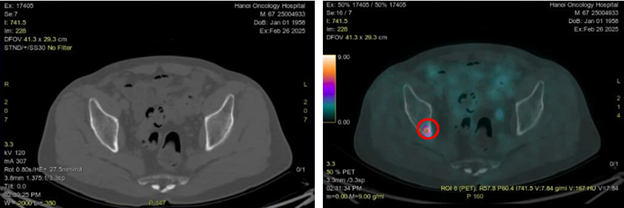

Hình 5: Hình ảnh hạch trung thất ở cửa sổ chủ phổi đường kính 7 mm trên CT (vòng tròn màu vàng) và PET/CT (vòng tròn màu đỏ) tăng chuyển hóa FDG (SUVmax: 2,69)

Hình 6: Hình ảnh CT cấu trúc bình thường (bên trái) và hình ảnh tăng hoạt tính phóng xạ ở xương ức trên PET/CT (vòng tròn màu đỏ) (SUVmax: 18,1)

Hình 7: Hình ảnh CT cấu trúc bình thường (bên trái) và hình ảnh tăng hoạt tính phóng xạ ở xương chậu phải trên PET/CT (vòng tròn màu đỏ) (SUVmax:7,84)